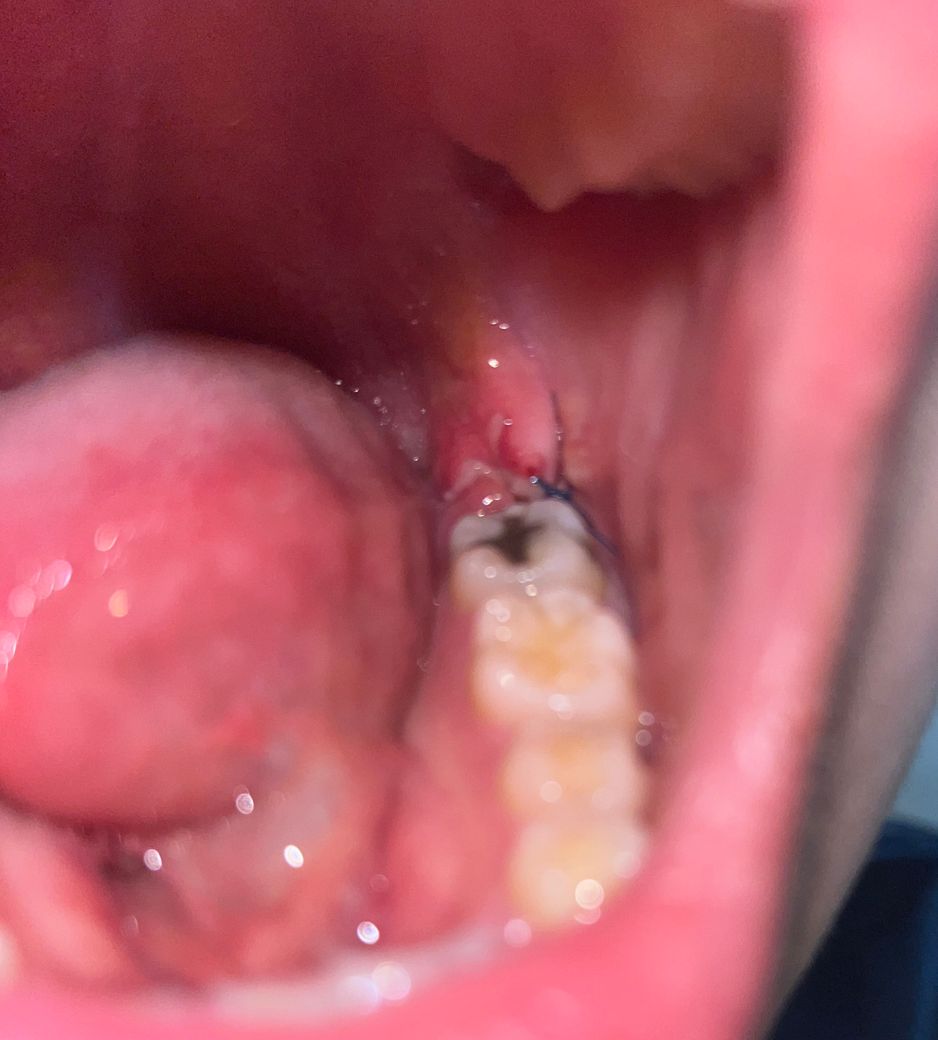

사랑니발치 3일차입미다. 드라이소켓인가요?

반매복 사랑니 발치하고 3일차입니다.

혈전?혈병?은 안 보이고 흰색만 보이는데

혹시 떨어져나가고 드라이소켓이 생긴거아닐까하고 물어봅니다! 혹시몰라 사진 첨부합니다

사진에는 특별히 이상이 보이진 않지만 통증의 정도가 심해지거나 냄새가 많이 나면 치과 가보셔야 합니다.

사진상으로 드라이 소켓은 아닌거 같습니다. 잇몸상처가 아직 낫지 않아서 그러는거 같으니 너무 걱정은 안하셔도 될것같습니다.

보통 드라이소켓은 악취, 통증이 심합니다 사진으로는 괜찮아보이고 흰색은 치유과정에서 생기는 염증,육아조직으로 보입니다